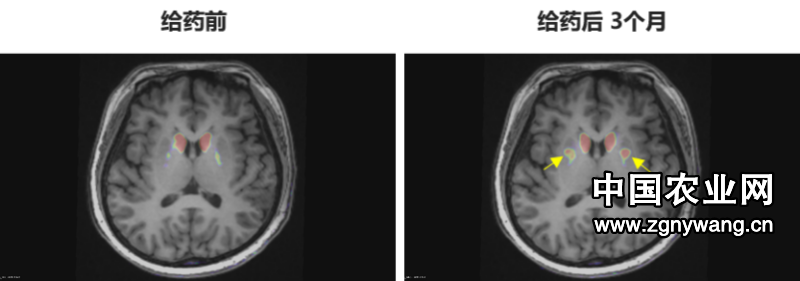

多巴胺能功能成像:神经突触多巴胺能显像是评估人脑黑质纹状体神经元完整性和功能的“金标准”,常用于帕金森病亚临床诊断1-2。接受移植手术3个月后PET-DAT/MRI融合影像明确显示,移植细胞已在患者脑内定植并成功转化为有功能的多巴胺能神经元,双侧纹状体形成显著的de novo新生多巴胺能活性成像(如下图箭头所指), 为功能性治愈提供了最直观的证据。

EOPD患者PET-DAT/MRI融合图像术前与术后三个月对比

注:影像图中黄色箭头指示为NCR201移植后,双侧纹状体出现的新生多巴胺能活性信号,提示移植细胞已定植并高效转化为功能性多巴胺能神经元